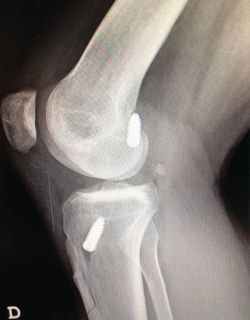

Planificación preoperatoria

Un diagnóstico y una planificación correctos son fundamentales. En caso de rotura de plastia del LCA (Figura 3), se hace obligatoria, además de una detallada exploración, un correcto estudio radiológico completo que incluya radiología convencional y resonancia magnética (RM) –estudio de lesiones acompañantes o degeneración previa–. En ocasiones en donde la anamnesis/exploración lo justifique, pueden ser también necesarias telemetrías de extremidades inferiores, radiología forzadas (si existiera inestabilidad mediolateral) o tomografía axial computarizada (TAC) –valoración de la posición y la calidad de los túneles–.

Figura 3. Rotura de la plastia del ligamento cruzado anterior.

La literatura ha identificado diferentes grupos de riesgo altamente expuestos a un fracaso de la cirugía del LCA. Pacientes hiperlaxos, mujeres jóvenes o con una alta demanda funcional (deportes de pivotaje) tienen cifras mayores de fracaso(10,12). El estudio detallado de estos casos, así como la identificación de posibles factores agravantes –pendiente tibial(13), eje mecánico varo-valgo, escotadura intercondílea estrecha(14)(Figura 4)–, pueden hacer necesario añadir gestos quirúrgicos correctores, como son la osteotomía tibial, el remodelado de la escotadura intercondílea o una plastia extraarticular de refuerzo (Figura 5).

Figura 4. Escotadura intercondílea estrecha. Forma de “catedral gótica”.

Se considera que una pendiente tibial > 13° genera una sobrecarga mecánica de la plastia en extensión(13). Existen en el mercado placas específicas de osteotomía proximal de la tibia especialmente diseñadas para evitar conflicto entre el túnel tibial y los tornillos de dicha placa.

Figura 5. Remodelado intercondíleo (aspecto final de “catedral románica”).

Figura 16. Túnel tibial excesivamente anterior, riesgo de pinzamiento de la plastia, flexo, extrusión meniscal o rotura de la cortical anterior tibial.

En rodillas con un recurvatum (será necesario explorar ambas rodillas previamente) puede ser interesante retrasar ligeramente a posterior la emergencia intraarticular del túnel tibial con la intención de minimizar el posible pinzamiento de la plastia en hiperextensión, o bien realizar un remodelado de la escotadura intercondílea. Asimismo, en las insuficiencias crónicas del LCA se observa con más frecuencia este cierre o estrechamiento de la escotadura intercondílea que puede comprometer nuestra plastia en extensión –en forma de catedral gótica (Figura 4)–. En estos casos, es necesario realizar una condiloplastia para aumentar el espacio intercondíleo –en forma de catedral románica (Figura 5)–.